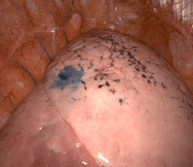

Mini-sonde endobronchique

De quoi s’agit-il ?

Cette technique nécessite un fibroscope bronchique, c’est-à-dire une caméra miniaturisée permettant d’explorer le poumon et les bronches de l’intérieur, par les voies naturelles.

La minisonde est une sonde de 2 mm qui s’insère dans le fibroscope permettant compte tenu de sa petite taille d’ aller plus loin dans les bronches de petit calibre. Cette minisonde est elle-même équipée d’une sonde d’échographie, miniaturisée à l’extrême, permettant d’examiner le poumon de l’intérieur.

A quoi ça sert ?

Ainsi des cancers à des stades plus précoces qu’auparavant peuvent être repérés et opérés.